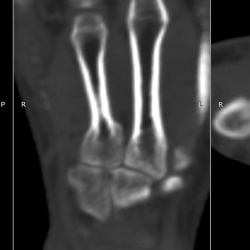

Здравствуйте, в 2014 случился надмыщелковый косом перелом правой плечевой кости со смещением, в качестве лечения были поставлены пластины, которые начали отторгаться и открылись два свищевых...

Здравствуйте, девушка 20 лет, случайная находка, подскажите это простая костная киста? ни че что она сообщается с полостью сустава? что рекомендовать?